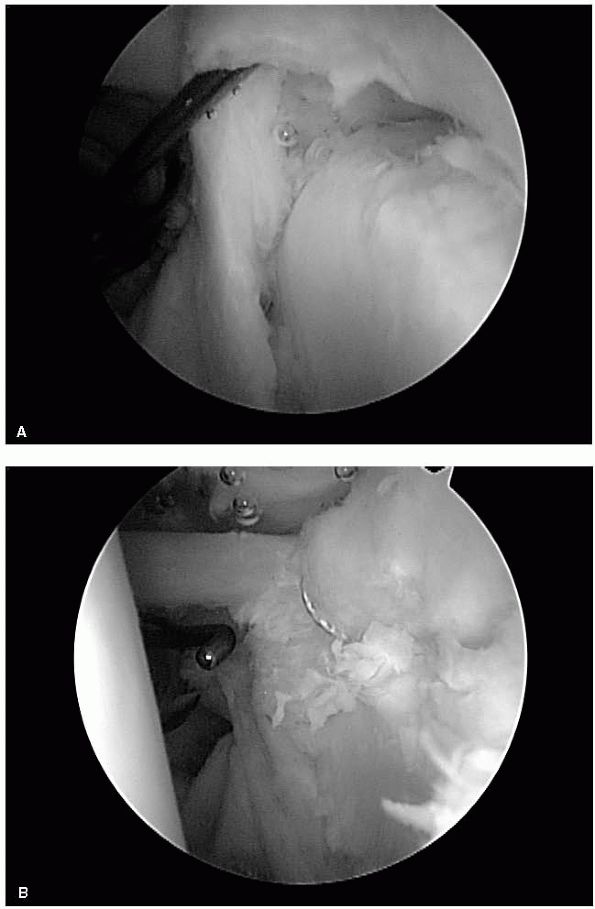

radiographic diagnosis of rotator cuff pathology. The advantages of MRI

ability to measure tear size and extent of retraction (Figure 12-31).

In addition, MRI can evaluate other associated abnormal conditions such

as degenerative acromioclavicular or glenohumeral changes, muscle

atrophy and fatty degeneration, capsular and labral pathology, biceps

rupture or dislocation, and ganglion cysts (Figure 12-32).

Through compression of the suprascapular nerve, these ganglion cysts

may produce signs and symptoms mimicking those of a rotator cuff tear.

![]() |

|

FIGURE 12-32. Coronal (A) and axial (B) MRI images of a ganglion cyst (white arrows) compressing the suprascapular nerve.

FIGURE 12-33. (A) Coronal MRI image of a partial-thickness rotator cuff tear (white arrows). (B)

Three years later, MRI of the same patient demonstrating a full-thickness tear of the rotator cuff with retraction of the supraspinatus tendon (white arrow) to the glenoid rim. |